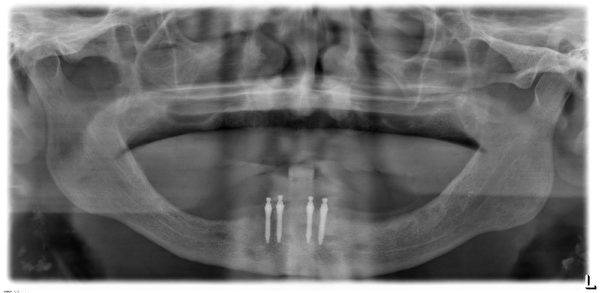

人工牙根能有效的取代缺牙,它是一种模仿牙根的钛金属,有着不同的直径、长度,医生可以依照植牙计划将其植入到患者的上颌或者下颌缺牙部位。

种植体是怎样植入的?

人工植牙是一种小型的局部麻醉门诊手术,依据缺牙的部位不同,大约需要20分钟至60分钟或更久。种植体植入牙槽骨后,经数月形成良好的骨整合后,就可以进行牙龈成型,然后就可以制作义齿完成上部修复。

目前新加坡有两种植牙技术,一种是迷你植牙,用细小的螺丝来固定牙齿,直径只有约两毫米。

另一种是传统植牙,用的金属比较厚,植一颗牙大概要3000元到5000元,疗程也较长,一般为半年,因为有些需动手术,加强骨头支撑度后才能植牙。